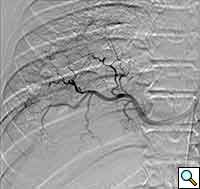

A previously healthy 43-year-old male presented with cough, fevers, and leukocytosis. A chest radiograph (Figure 1) revealed extensive consolidation in the right lower lung containing multiple cavities with air-fluid levels consistent with a necrotizing infection. A chest computed tomogram (Figure 2) showed an abscess cavity and consolidation in the right lower lobe with an aberrant blood supply from the descending aorta. This systemic blood supply was confirmed by subsequent 3D reconstruction (Figure 3). He was initially treated with IV antibiotics, resulting in normalization of his temperature and white blood cell count. He was then discharged home on a 3-week course of oral antibiotics. Three days prior to a planned surgical resection, he underwent angiographic localization of the feeding artery (Figure 4) and coil embolization (Figure 5).